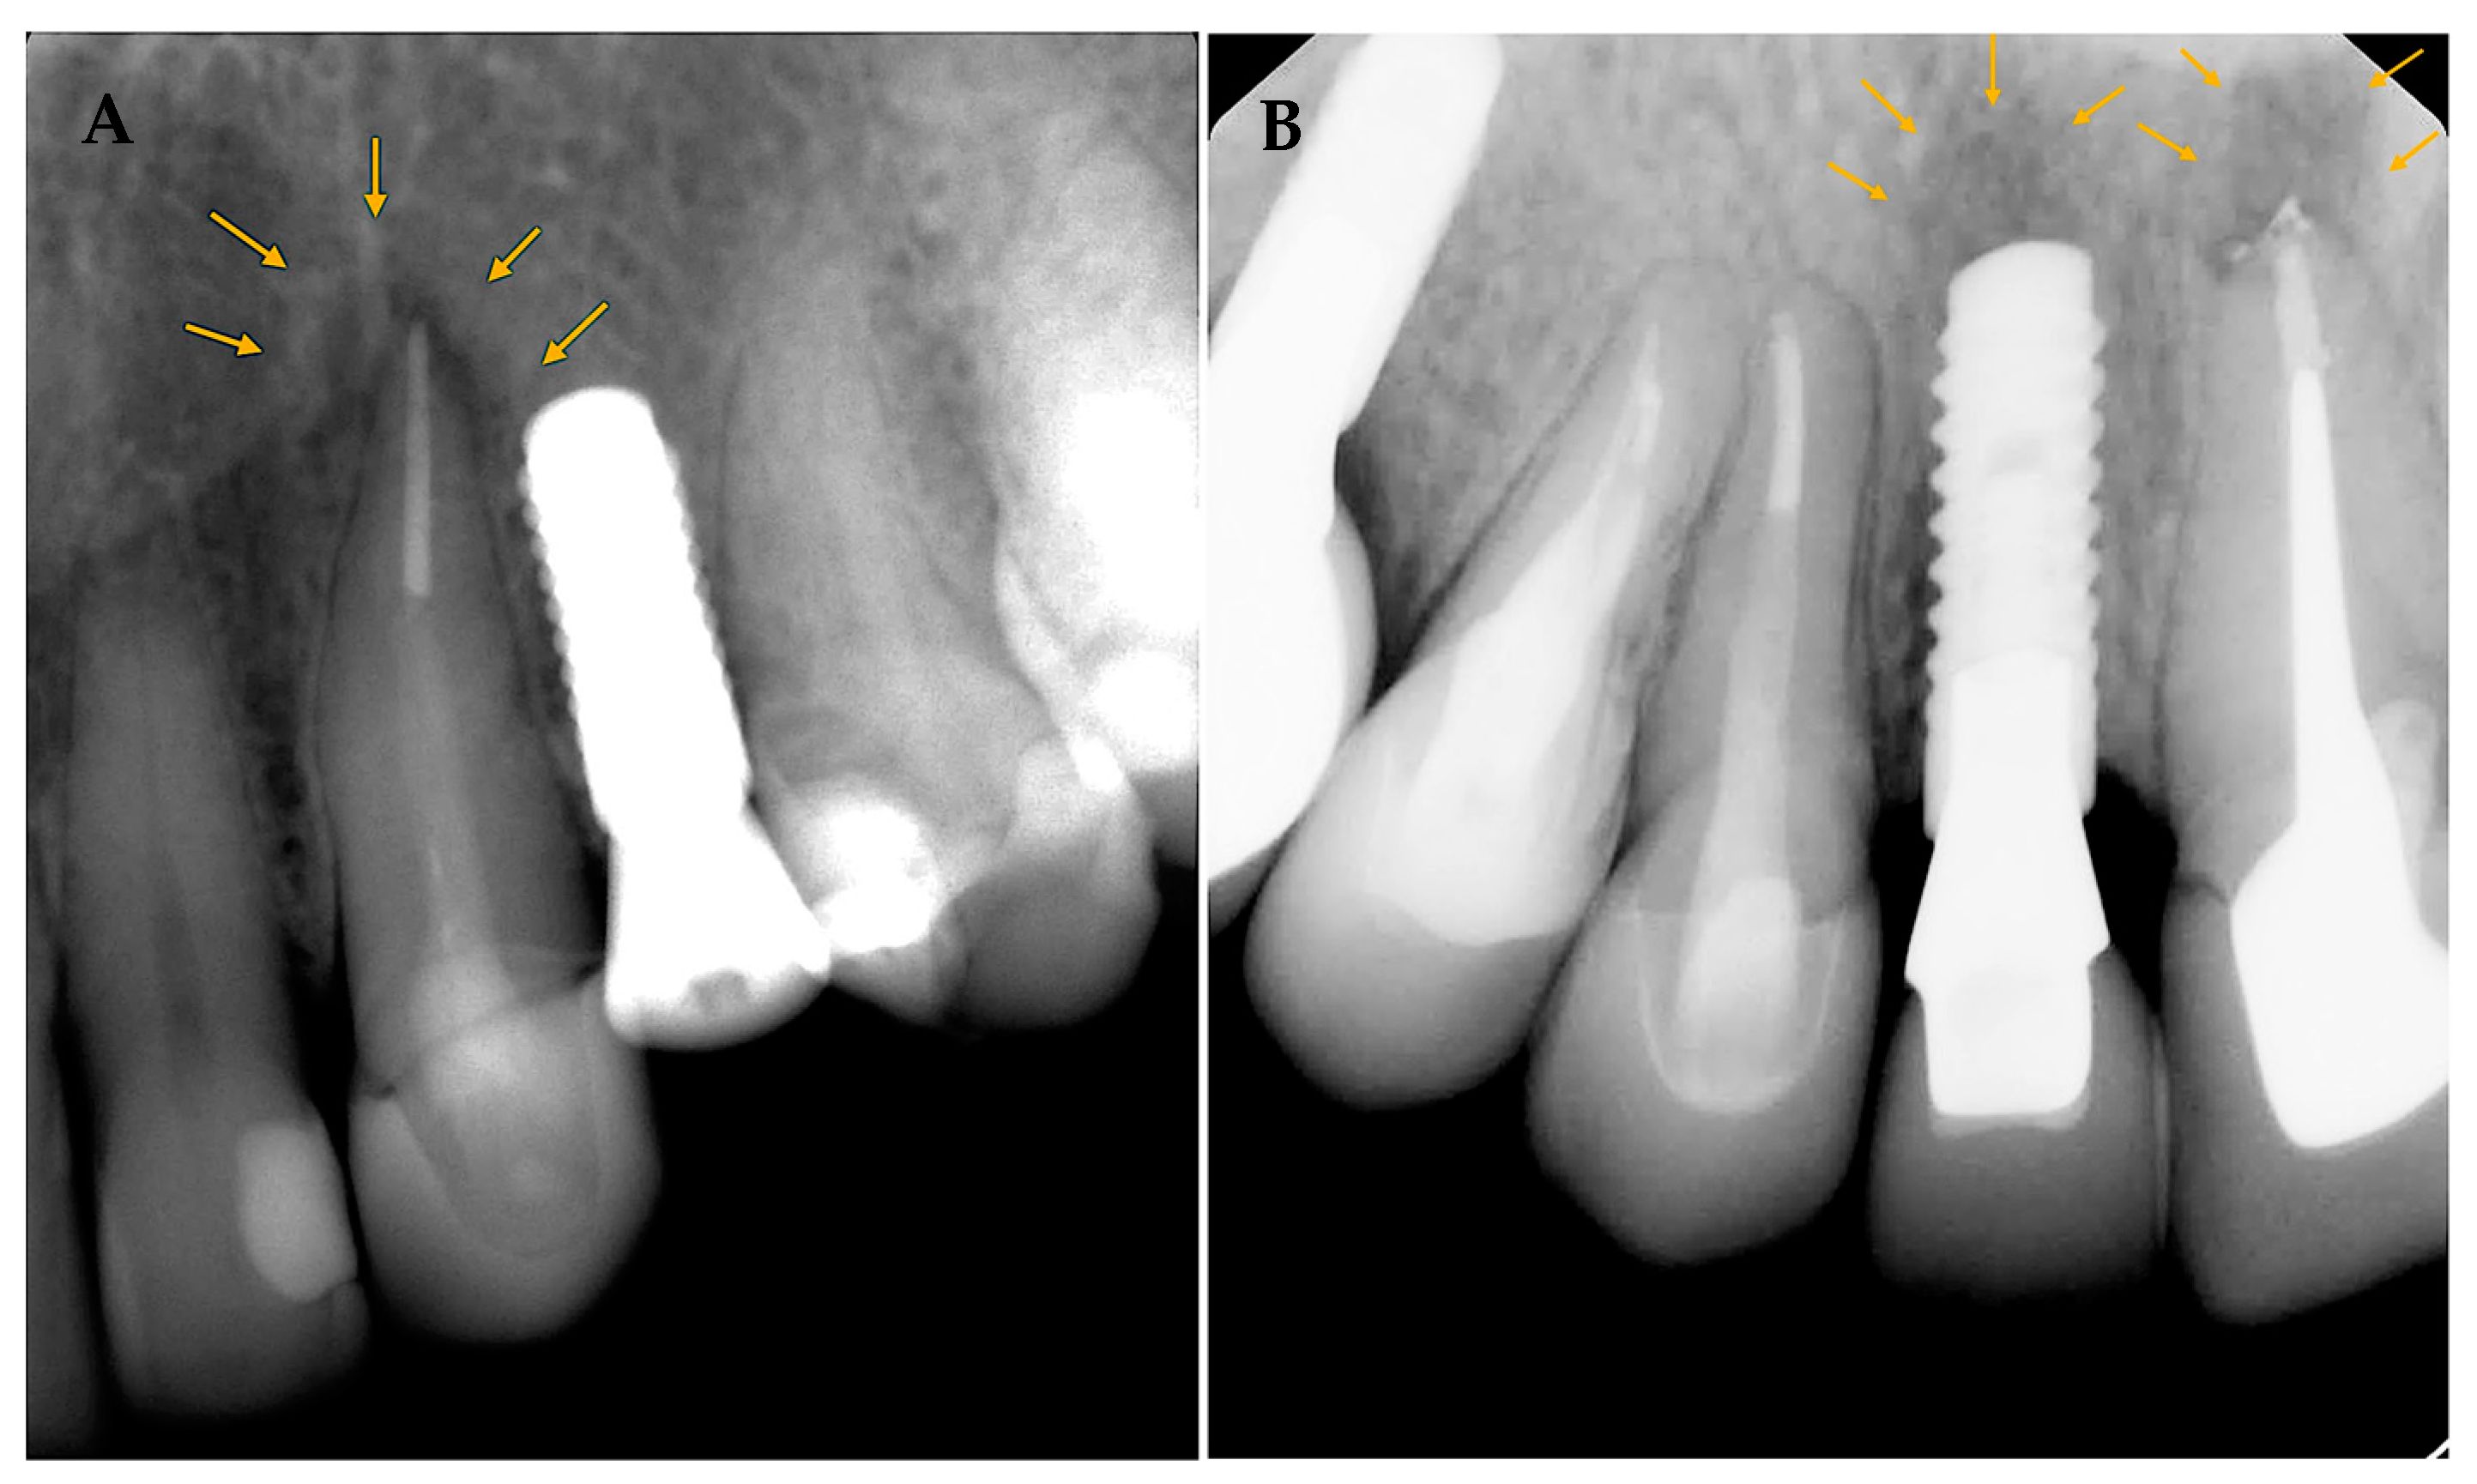

Only two sites from the whole sample (0.9%) were confirmed as RPI. Both are from the EI group and account for 2%. In addition, the two implants placed next to endodontically involved teeth (category A) represented 3.4% of that category. A total of 10 cases showed PAL around adjacent endodontically treated teeth, and two of them developed RPI, accounting for 20% incidence in cases where adjacent endodontically treated teeth have PAL. Both instances show proximity to the adjacent teeth (was ≤3 mm).

Patients were brought for further clinical and radiographic evaluations for the cases diagnosed with RPI. Case 1 (Figure 3A) 56 years old female with a history of hypothyroidism (taking thyroxine). Tooth #24 was extracted, and the implant was placed more than 12 months after extraction (delayed implant placement protocol). Although the reason for extraction was not stated, RL developed around the implant body soon after implant placement and before loading. A diagnosis of asymptomatic reversible pulpitis was made for adjacent tooth #23, and endodontic treatment was initiated. No further treatment was performed, and the final restoration was placed after a few months. The implant was stable at the follow-up visit 4 years later.

In case 2 (Figure 3B), 38 years old healthy female presented to replace an old fixed partial denture replacing teeth # 11–13 with 2 single crowns and an implant in the area of tooth #12. Both #11 and 13 had a previous root canal treatment. #11 had a PAL, and re-treatment was initiated before implant placement at the area of tooth #12. A few days later, the implant was placed at #12 (delayed implant placement protocol); soon after implant placement and before loading, RL developed around the implant body. Endodontic re-treatment was initiated on tooth #13. A few months later, the final implant restoration was placed. The implant was stable at the follow-up visit 4 years later.

Figure 3. (A,B) show implant cases with RPI. Arrows to outline the periapical lesions in relation to teeth and adjacent implants.